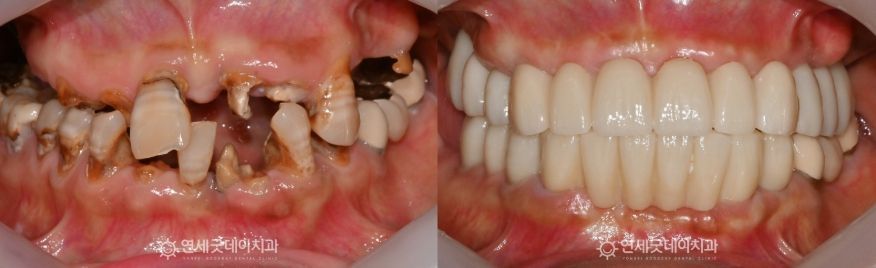

Case Review

Full Mouth Implant Before & After